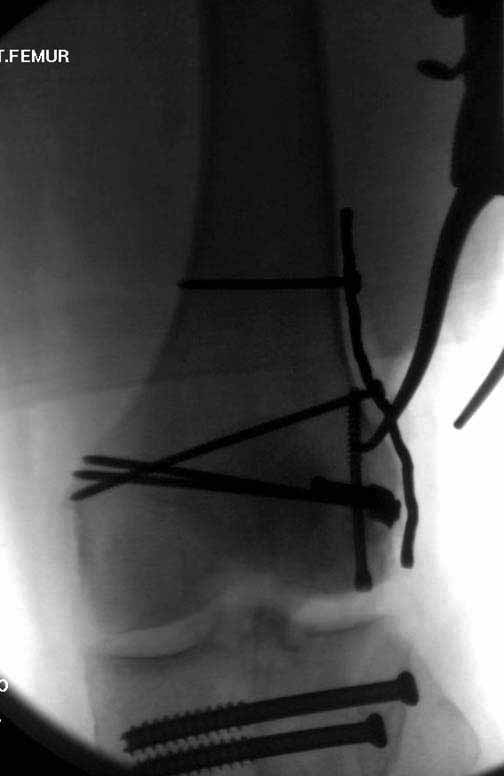

Ну зачем же так. Всё-таки считается "золотым стандартом". Во вложенном файле коллаж из сохранившихся фотографий одной из операций. Всё сделано закрыто и без ЭОПа.

Ответ на эту часть Вашего поста – вложенный файл. Больная оперирована неделю назад по поводу открытого перелома дистального эпиметафиза бедренной кости. После операции она идёт в рентгенкабинет для выполнения послеоперационной контрольной рентгенографии, представленной на слайдах 10 и 11. Узнав, почему её фотографируют, просила передать Вам, Антон, привет.

Антеградное штифтование не очень годится при переломах типа C3, когда есть многооскольчатость именно суставной поверхности. А при переломах типа C1 и С2, т.е. и в обсуждаемом случае тоже, он как раз вполне оптимален. На межфрагментарную компрессию как-то не приходилось так драматически полагаться при интрамедуллярном остеосинтезе, результаты хорошие без нее были.

В этой терминологии мы, получается, создавали компрессию встречными спицами с упорами или reduction clamps, а потом вполне обходились запирающими винтами как позиционными. Бывает, проводим 1-2 спонгиозных винта 6,5-8 мм - вот они вполне компрессирующие.

И уже лет шесть мы используем возможность ввести в дистальное овальное отверстие 3 винта, которые именно запираются в этом отверстии, не люфтят, а обеспечивают угловую стабильность - см картинку.

Получается и стабильно, и очень дистально, нижний край отверстия в 3 мм от дистального конца гвоздя.

В приложении пример недавней операции, C3, открытая репозиция, фиксация мыщелков спицами и винтами, ретроградный синтез большеберцовым гвоздем 10,5 мм диаметром, винты 5 мм.